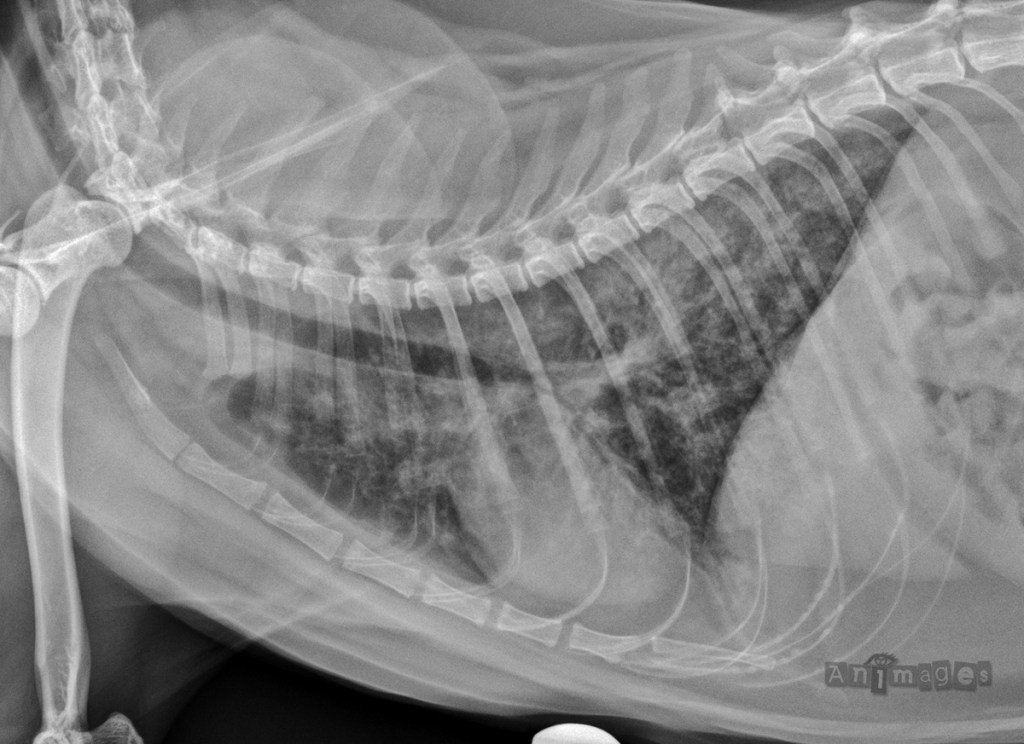

Latérale gauche du thorax